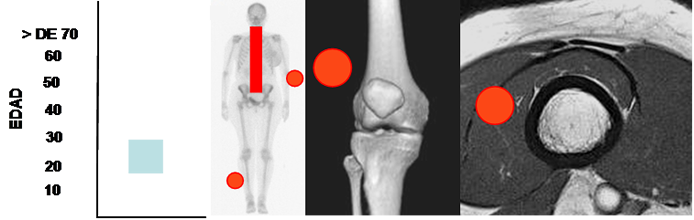

Son comunes entre los 20 y 30 años y compromete los nervios espinales, la cadena simpática de cuello y cara y las extremidades, con predominio en el ulnar y el peroneo. (45). (Fig 173 A).

Fig 173 A. Schwanoma.

Mayor frecuencia entre los 20 y 30 años. Lesión de tejidos blandos con predominio en nervios paraespinales, cadena simpática, nervio ulnar y peroneo.